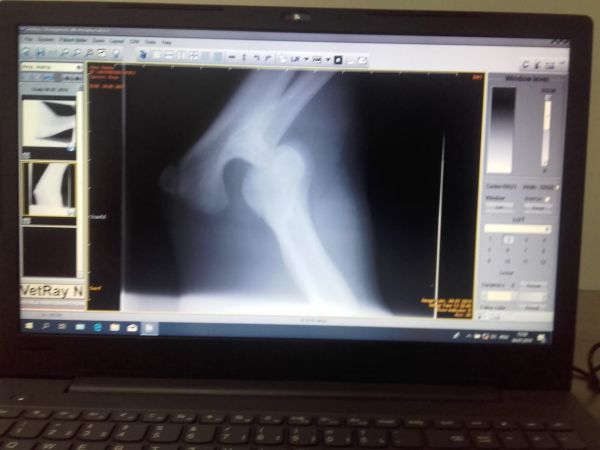

Anima, ursoaica lovită de mașină pe DN1, a trecut printr-o nouă procedură medicală.

Astăzi i-a fost făcută o radiografie care a confirmat temerile medicilor veterinari colaboratori ai AMP: fractură de femur cu deplasare la piciorul drept, spate. Radiografia a scos însă la iveală și o problemă mai veche, la piciorul drept-față al ursoaicei: o luxație de articulație, cu posibilă ruptură de ligamente.Rezultatele vor ajunge astăzi în Germania, la medicul veterinar specialist care sperăm să o opereze pe tănăra ursoaică. Acum așteptăm cu toții costurile estimative ale intervenției, dar și o dată aproximativă în care poate fi efectuată operația.[gallery columns="4" size="medium" link="file" td_select_gallery_slide="slide" td_gallery_title_input="Foto: Asociația Milioane de Prieteni Brașov" ids="58351,58352,58353,58354"]